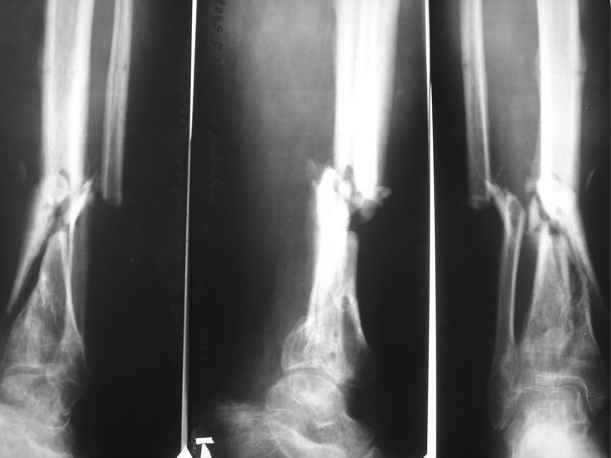

Ложный сустав большеберцовой кости

Пациент 35 лет, травма в декабре 2007 г. Открытый оскольчатый перелом костей левой голени в нижней трети со смещением отломков. Травма в результате ДТП. В этот же день выполнена ПХО открытого перелома костей левой голени, скелетное вытяжение. На 3 день ЧКДО с учетом повреждения мягких тканей. Посттравматический период осложнился обширным циркулярным некрозом кожи. Через этапные некроэктомии, и свободную кожную пластику раны зажили вторичным натяжением. По заживлении мягких тканей перемонтаж аппарата. Выписан на амбулаторное лечение. В августе 2008 г. из за выраженного воспаления в местах выхода спиц, аппарат демонтирован. Явления воспаления купированы. Данных за остеомиелит не получено. На данный момент имеем: ложный сустав левой большеберцовой кости в нижней трети. Укорочение левой нижней конечности на 3 см. Комбинированная контрактура левого голеностопного сустава. Клинически – патологическая подвижность в области перелома. Лабораторные показатели в пределах нормы. Местно воспалительных явлений мягких тканей нет.

1. Вариант № 1(основной) – в два этапа. 1. Наложить спице-стержневой аппарат, за 5 – 7 – 10 дней устранить смещение отломков (восстановить ось большеберцовой кости). 2 этап закрытый блокированный остеосинтез цельным гвоздем диметра 10 – 11 мм для низких переломов голени (Эксперт, Мастер…). Сначала в статику на 2-3 недели, затем динамизацию.

1.Достаточна ли длина дистального отломка для жесткой фиксации на гвозде ( как минимум на 3 винтах)?

2. Как будут проходить гибкие риммеры через область ложного сустава при рассверливании костно – мозгового канала?

3. Возможно ли выполнить закрытый блокируемый остеосинтез без предварительного наложения КДА?

4. Где могут быть технические трудности?

Вариант №2 КДА по Илизарову, работать в аппарате, устранить смещение, компрессия, дистракция.

Вариант № 3. КДА по Илизарову , + костная пластика из крыла подвздошной кости кортикально -губчатым трансплантатом, или из малоберцовой кости.